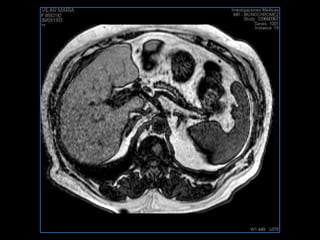

PROTOCOLO hígado graso AXIAL in phase y out phase AX T1 y AX fat sat +SAG T2  CON   GADOLINIO :  COR T1+AX T1(DIN) SAT: NO  FASE: RL THK: 4MM  COIL:  GAP: (FACTOR 1.4)  FOV: 40 CM NEX:2 SINCRONIZACION RESPIRATORIA EN 3 O 4 CICLOS ALE

PROTOCOLO hemocromatosis AXIAL supresión grasa /AX multieco en higado COR T2 AX T1 +SAG T2  CON   GADOLINIO :  COR T1+AX T1 SAT: NO  FASE: RL THK: 4MM  COIL:  GAP: (FACTOR 1.4) 1MM FOV: 40 CM NEX:2 SINCRONIZACION RESPIRATORIA EN 3 O 4 CICLOS ALE